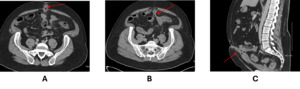

A CT scan revealed an elongated bladder in the midline, along with a fistulizing connection between the umbilicus and the sigmoid colon. A diagnosis of a urachal-sigmoid fistula was established (Figures 1). The patient was started on ciprofloxacin, metronidazole, and neomycin, which provided immediate relief. The patient was bowel prepped for resection, during which he experienced copious liquid discharge from the umbilicus. The procedure began as a laparoscopic resection but was converted to open due to the size and extent of the urachus. The urachus was carefully dissected and removed down to the base of the bladder, followed by sigmoid resection with primary anastomosis. The patient was discharged on postoperative day 5 and was doing well at his outpatient follow-up.

_and_sagittal_(c)_ct_images_depicting_the_urachal-sigmoid_fistula_(arro.png)